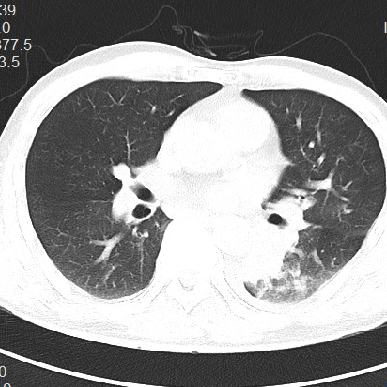

6.25日当地胸部而增强CT

•胸部增强CT(6.29)示双肺多发病变,以左肺下叶为著,部分包绕左肺门,为肺黏液腺癌不能排除,炎性病变待除;纵隔内多发小及稍大淋巴结;左侧胸膜增厚,左侧胸腔少量积液”,考虑“肺部感染”,予莫西沙星(6.30)静滴抗感染,上述症状未见好转。今为进一步治疗,以“肺部感染”收住入院。

6.29